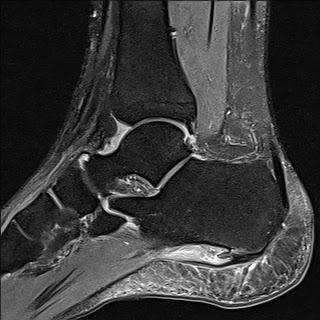

실제로 아래와 같이 X-ray 나 MRI 에서 쉽게 발견할 수 있습니다. (잘 안보이는 경우 내측으로 45도 비스듬하게 찍기도합니다.) 골극은 주로 FDB의 기시부에 위치합니다. 본 스캔 검사를 통해서(핵의학검사) 족저근막염을 확인해 볼 수도 있습니다.